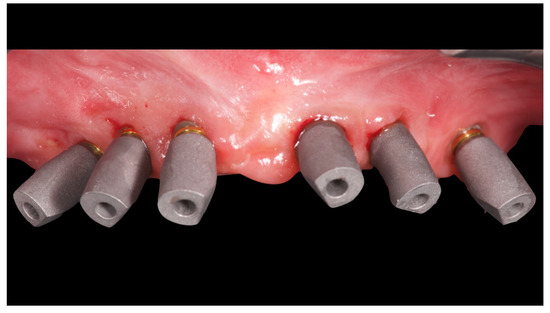

Before definitive impression, multi-unit abutments were unscrewed, the implant connections were cleaned, and six OT Equator Titanium Abutments (Rhein’83, Bologna, Italy) with TiN coating were screwed (Figure 6), according to the manufacturer. Immediately after, the patient received a digital impression (CS 3600 intraoral scanner, Carestream Dental, Milan, Italy), taken at abutment level (Figure 7), using dedicated scan abutments (OT Equator Titanium Scan Abutment, Rhein’83). However, overlapping of the captured images failed to produce an accurate impression, maybe due to the disparallelism of the implant ranging from 65° to 86°. Hence, a prototype model was created and a convention gypsum impression [16] with a customized impression tray was taken at abutment level using conventional impression coping (Titanium Impression Coping, Rhein’83; Figure 8 and Figure 9). Esthetics, phonetics, the occlusal vertical dimension, and the centric relation were verified and approved by both the clinician and the patient (Figure 10 and Figure 11). Only after that, a definitive cast, implant position, and esthetic try-in were digitalized and a CAD/CAM titanium bar (NewAncorvis, Bologna, Italy) was anatomically designed with a dedicated software (Exocad DentalCAD, Exocad, Darmstadt, Germany) by a certified dental technician (MA), according to the prosthetic contours and the implant position. Three projects were created with a three-, two-, or one-piece CAD/CAM titanium bar, respectively (Figure 11b). Each of these projects failed to create an accurate titanium bar able to respect the minimum restorative space required by the prosthetic volume of the tried prosthesis, due to the multiple components involved (attachment system, prosthetic framework, artificial acrylic composite teeth, and pink acrylic base). Hence, a fourth project was created with a CAD/CAM titanium bar designed for a fixed screw-retained restoration, initially excluded due to the implant disparallelism. In order to overcome the undercuts created by the tilted implants, and to produce a passive-fit CAD/CAM titanium bar, abutments with an extragrade system were applied (Figure 11c). Extragrade is a special titanium abutment which has the possibility of entering, even in cases of strong disparallelisms, thanks to its internal design. On a large number of implants (those positioned worse from the point of view of the emergence profile), we cannot put the through screw. In this case, the abutment will be retained by the white Seeger only. The number of abutments without screws was limited to two, according to the manufacturer and considering the overall number of placed implants. Moreover, an angulated screw channel concept was applied to avoid the access hole in the vestibular area of the anterior teeth, moving the access holes in the pink area of the hybrid prosthesis. The fit of the implant bar was clinically and radiographically tested in the patient’s mouth, according to established criteria ([17,18,19]; Figure 12). It was important to position the flat surfaces of the abutment-bar connections in correspondence with the undercut created by the inclination of the implant; the flat surface indicates the location of the extragrade bevel, which allows the framework to overcome the undercuts created by the tilted implants. After that, an interocclusal record was taken in centric relation, and the prosthesis was delivered. The screw-retained fixed complete implant-supported prosthesis was seated in the patient’s mouth using the snap-on function offered served by the Seeger System (Figure 13). Four out of six screws were tightened according to the manufacturer, and the screw-holes were closed using composite pink materials. Finally, the occlusion was adjusted and radiographs were taken. The patient was scheduled for hygiene maintenance and control every 4 months (Figure 14, Figure 15 and Figure 16).

Figure 7.

Scan bodies mounted on OT Equator. Note the strong disparallelism among the dental implants.